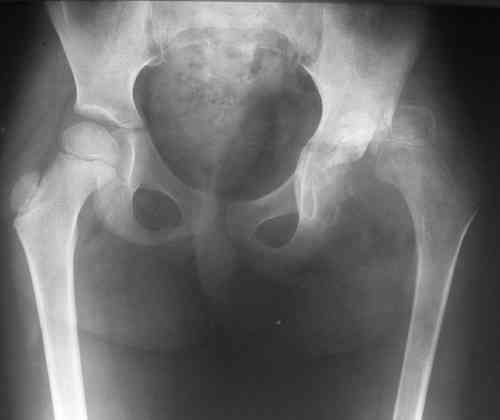

После операции ребенок находился в гонитной повязке три недели. Затем повязка снята. На контрольной рентгенограмме выявлен вывих левого бедра. Наложена система скелетного вытяжения за левое бедро. Через две недели система снята, наложена шина Веленского. Вопросы: 1. Тактика дальнейшего лечения? 2. Какое оперативное лечение оптимально предпринять? Заранее благодарю! С уважением, А.В.Владзимирский ДНИИТОDear colleagues! Female, 5 y.o. During 1 year she has pain and limitation of movements in left hip. DS: Osteochondroma of left hip. 26.07.07. surgery: arthrotomia, removing of osteochondroma, plastic of defects with “Tutoplast”, cast fixation. Cytology: parts of hyalin cartilage with sponge bone and marrow. Most possible – osteochondroma, osteochondro exostosis. Cartilage tissue not looks like typical chondroma. After 3 weeks cast fixation was removed. At x-ray – dislocation. Dislocation was treated by sceletal traction (2 weeks). Now – dislocation again. Question: Treatment? Which surgical treatment most useful in this situation? Thank you very much for your comments, opinions, ideas!!! Best wishes, Anton Vladzymyrskyy

2. Судя по представленному снимку, образование находилось внутрисуставно, а кости таза не поражены (что тогда заполнялось тутопластом? и не он ли, судя по п\о рентгенограмме явился причиной вывиха?).

А бедро надо возвращать ко впадине дистракцией, иначе в дополнение к впадине и головку угробить недолго. Видимо в дальнейшем не обойтись без пластики наружного края вертлуги.